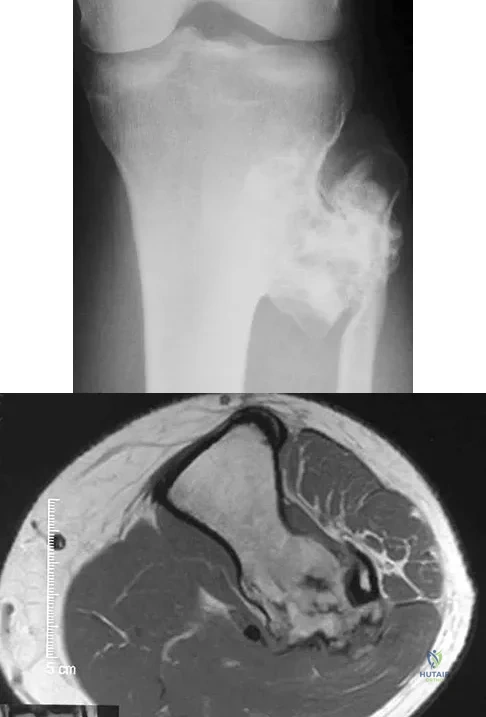

A 58-year-old woman has a fracture through a metacarpal lesion after a motor vehicle accident. She denies any preinjury symptoms and the fracture heals uneventfully. Based on the radiograph and MRI scans shown in Figures 22a through 22c obtained following fracture healing, follow-up management should consist of

A 14-year-old girl reports bilateral patellofemoral symptoms. Based on the radiograph and MRI scans shown in Figures 23a through 23d, what is the next most appropriate step in management of the lesion?

A 13-year-old boy has knee pain after sustaining a mild twisting injury while playing basketball 4 weeks ago. Radiographs and MRI scans are shown in Figures 24a through 24d, and biopsy specimens are shown in Figures 24e and 24f. Treatment should consist of